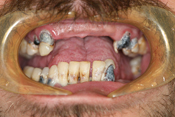

WORST TEETH Pictures from Warren Dentistry

This can happen to your teeth when proper Dental Hygiene is not practiced.

Patient 3